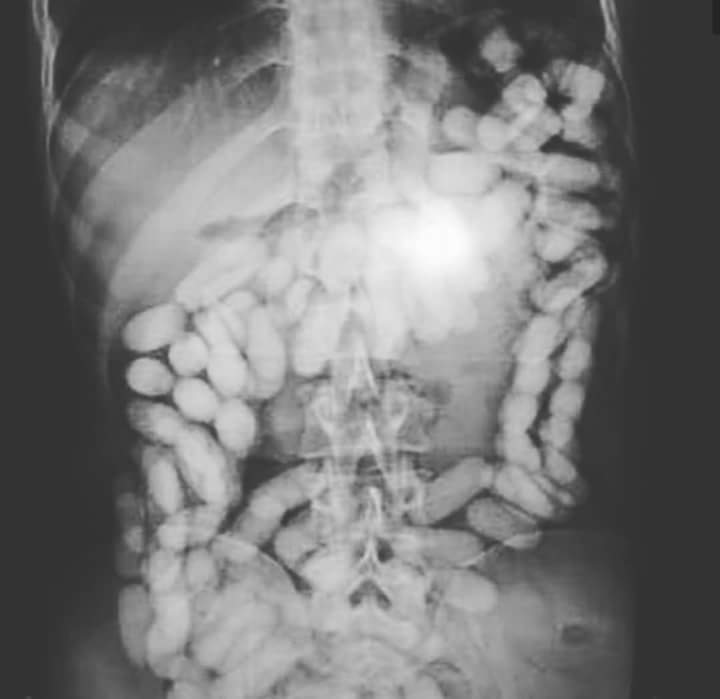

Con motivo de un control en uno de los vuelos llegado de Sudamérica, fue detenido un varón del que se pudo constatar a través del sistema de rayos X que portaba droga en su cuerpo.

Una vez detenido el viajero e ingresado en el hospital fue expulsando hasta un total de 50 cilindros con cocaína, que contenían cerca de 400 gramos. Tras el incidente, el Grupo I del Grupo de Estupefacientes, se hizo cargo de las investigaciones.